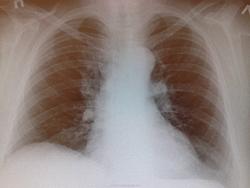

Ж., 64 года, без легочных жалоб. Волнует правый корень - он просто такой ветвистый, сосудистый или нет? смущает зона гиповентиляции над ним. Интересно ваше мнение.

Попробуйте переснять. Чутка левым боком поближе, а правым от стойки слегка отслонясь, градусов эдак на 5... Качество не позволяет мне этот корень для Вас и себя в покое оставить без дополнительного снимка пока.